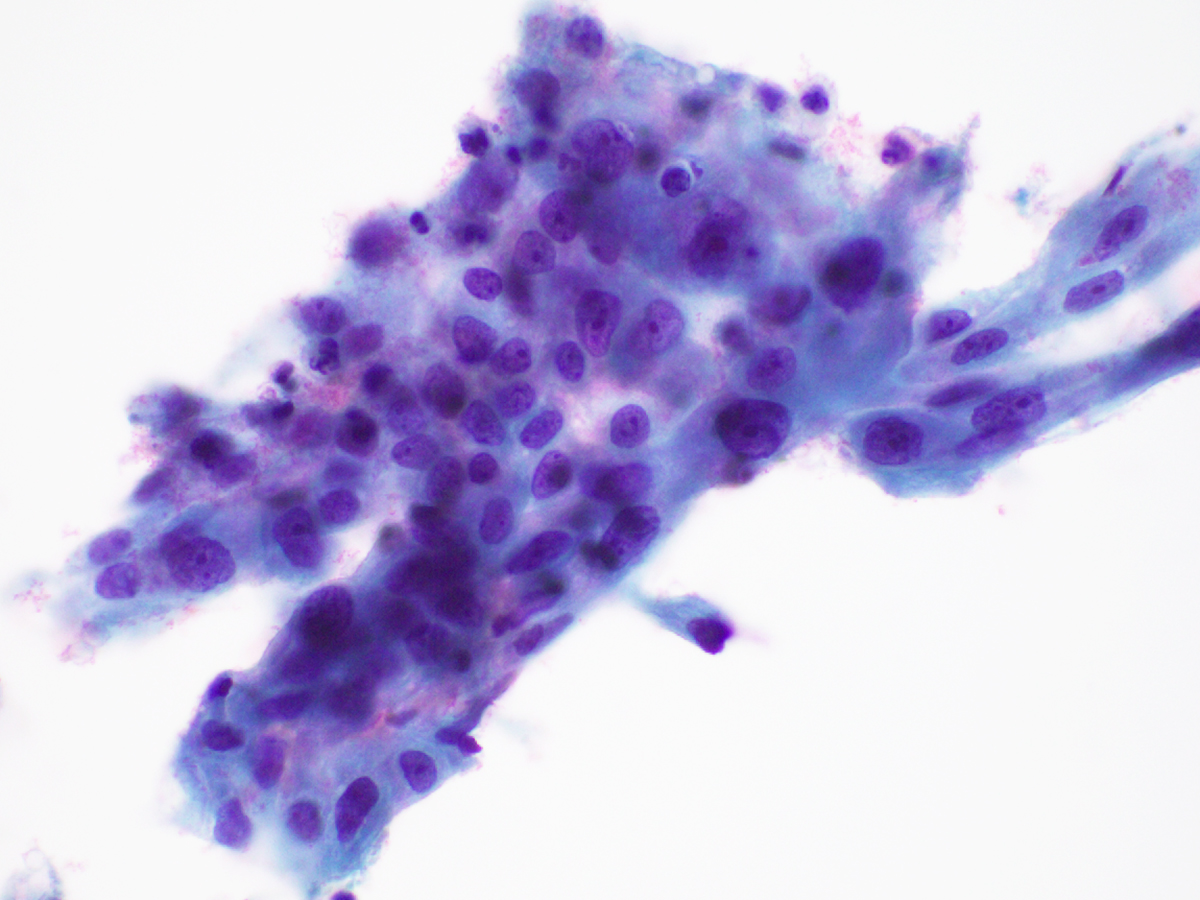

Figure 1. Cervical Pap test, ThinPrep, Papanicolaou stain, 400X magnification

Figure 2. Cervical Pap test, ThinPrep, Papanicolaou stain, 600X magnification

Figure 3. Cervical Pap test, ThinPrep, Papanicolaou stain, 600X magnification

On the ThinPrep, the cells are mostly seen in clusters or lying singly. They are large cells with well-defined moderate to abundant amounts of granular to vacuolated cytoplasm. The nuclear:cytoplasmic (N:C) ratio is variable and is focally increased. The nuclei are round to ovoid. The chromatin is mostly granular, the nuclear membranes are smooth to mildly irregular, and the nucleoli are prominent (Images 1-3). On the cell block section, decidua is seen in the form of flat sheets with round to polygonal epithelioid cells with well-defined eosinophilic cytoplasm. The nuclear characteristics are similar to that noted on the ThinPrep except that the chromatin is vesicular to granular (probably related to the differences in the stain) (Images 4-6).

The decidua cells can be easily misinterpreted as a significant squamous cell or glandular cell abnormality on cytology, owing to the overlap in their cytomorphology. ASC-H and HSIL cells, however, tend to show denser cytoplasm, coarser chromatin, more uniformly higher N:C ratios and pronounced nuclear membrane irregularities, and less apparent nucleoli. Atypical glandular cells of endocervical origin, unless originating from a higher grade adenocarcinoma, are typically more columnar with mild to moderate crowding and stratified, elongated hyperchromatic nuclei. Atypical glandular cells of endometrial origin usually exhibit more crowded three-dimensional groups with enlarged nuclei, granular to vesicular chromatin and prominent nucleoli.